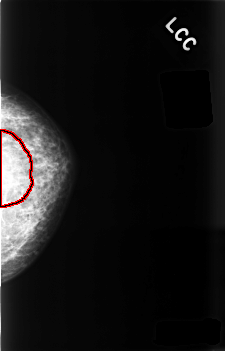

C_0481_1.LEFT_CC

LEFT_CC LINES 4552 PIXELS_PER_LINE 2920 BITS_PER_PIXEL 12 RESOLUTION 50 OVERLAY

FILE: C_0481_1.LEFT_CC.OVERLAY

TOTAL_ABNORMALITIES 1

ABNORMALITY 1

LESION_TYPE MASS SHAPE ASYMMETRIC_BREAST_TISSUE MARGINS ILL_DEFINED

ASSESSMENT 5

SUBTLETY 2

PATHOLOGY MALIGNANT

TOTAL_OUTLINES 1

BOUNDARY